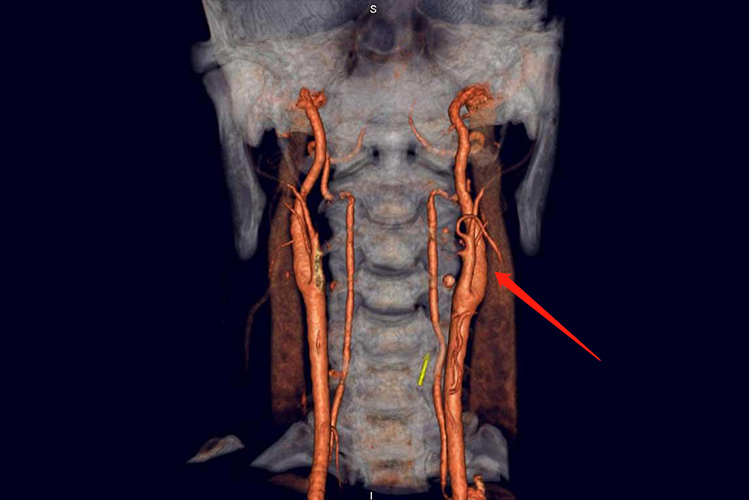

椎动脉型颈椎病:患者临床表现主要包括眩晕、视力障碍、头痛,以及猝倒。CTA检查常可见骨刺压迫椎动脉或者血管变异。